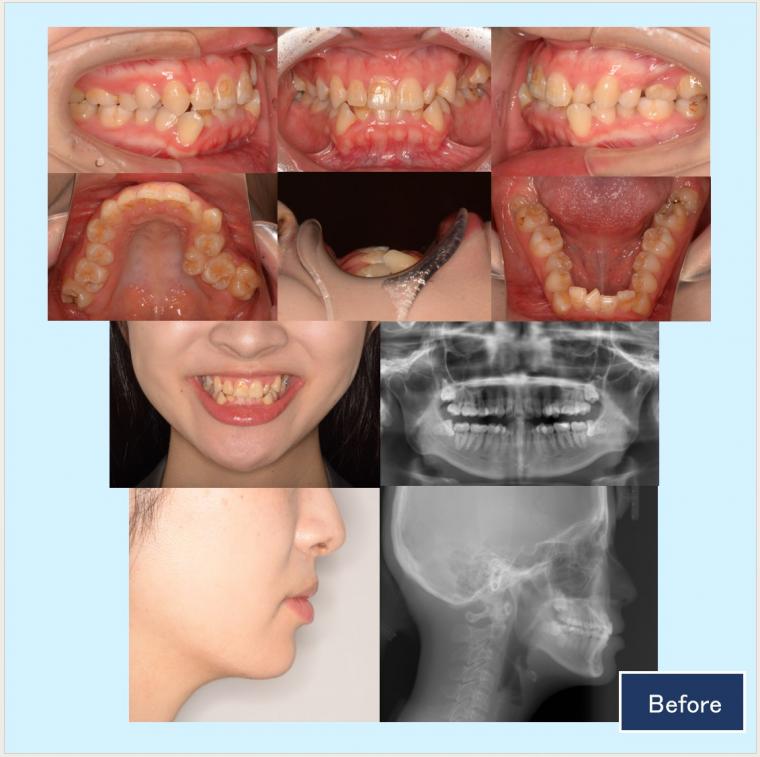

No.53 ハーフリンガルで歯列不整と狭窄歯列を改善した症例

20代女性 千葉県市川市

『下唇が犬歯の出っ張りに引っ掛かるほど歯がガタガタしている。歯ぐきの見え方も減らしたい』という主訴でした。

診断名:重度叢生、軽度下顎前突症例

年齢:20代 治療期間:2年3ヵ月 治療回数:26回